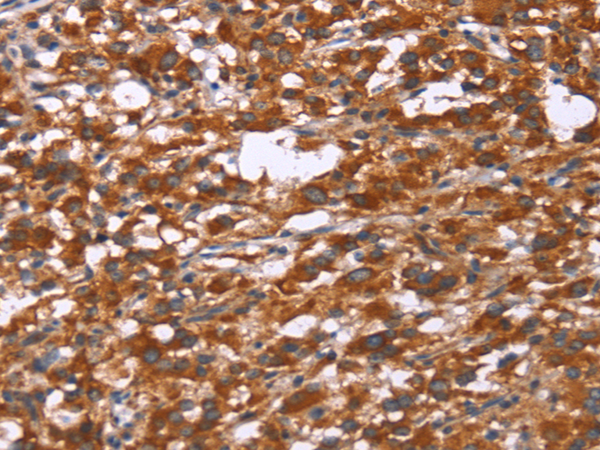

中文名稱: 兔抗GPHN多克隆抗體

英文名稱: Anti-GPHN rabbit polyclonal antibody

ELISA, IHC

IHC positive control:

Human thyroid cancer and Human gastric cancer

IHC Recommend dilution:

50-200